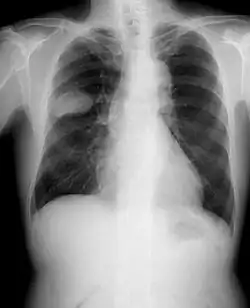

Frontal chest X-ray showing a probable S2–S3 small cell carcinoma in the right side lung.

Small-cell carcinoma of the lung usually presents in the central airways and infiltrates the submucosa leading to the narrowing of bronchial airways. Common symptoms include cough, dyspnea, weight loss, and debility. Over 70% of patients with small-cell carcinoma present with metastatic disease; common sites include the liver, adrenals, bone, and brain.[24][25]